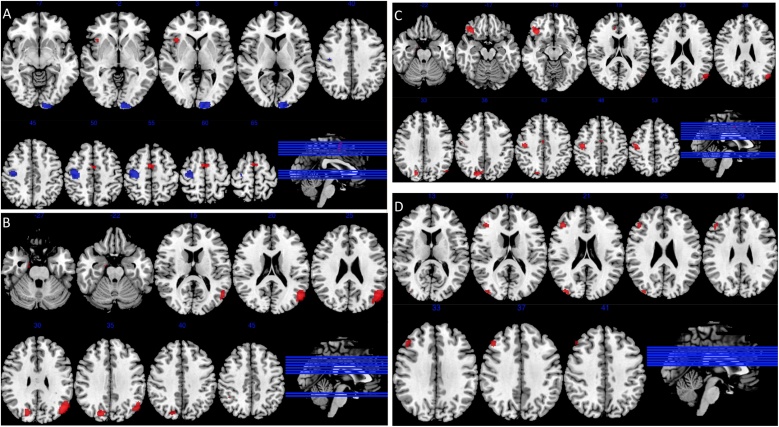

All studies qualifying for the ACU group, were carried out in adolescent users. Further meta-analysis comparing ACU and CCU, using only adolescent studies was completed. Data from three manuscripts reporting on current adolescent users, with four separate comparisons, with 69 CCU and 70 NU were used for comparison with the abstinent adolescent user group described above. Results for all meta-analyses are reported in Table 3 and Fig. 2.

Adult and adolescent CCU compared to NU

Meta-analysis of CCU revealed that CCU had increased activation when compared to NU in the medial frontal gyrus bilaterally and right insula, extending ipsilaterally to the inferior frontal gyrus. A decrease in activation was found in CCU compared to NU in the left cuneus, extending ipsilaterally to the superior, middle, and inferior occipital gyri; and in the right precentral gyrus, (k = 22; CU n = 361, NU n = 394).

Adolescent ACU compared to NU

Meta-analysis of adolescent ACU compared to NU revealed that ACU had increased activation in the right inferior frontal gyrus; right precuneus, extending ipsilaterally to the superior parietal gyrus; and the right middle occipital gyrus, extending ipsilaterally to the superior occipital gyrus and cuneus; the middle frontal gyrus extending to the superior frontal gyrus bilaterally and the inferior parietal gyri bilaterally, extending to the superior parietal gyrus bilaterally and the right angular gyrus. There were no areas where brain activation was significantly decreased in ACU compared to NU (k = 5; CU n = 98, NU n = 106).

Adult and adolescent CCU compared to adolescent ACU

Meta-analysis comparing CCU including both adult and adolescent studies to adolescent ACU, revealed no areas where brain activation was significantly increased in CCU compared to ACU, However, ACU had increased activation in the right precuneus, extending ipsilaterally to postcentral and superior parietal gyrI; the left lingual gyrus, extending ipsilaterally to superior and middle occipital gyri; the left middle frontal gyrus extending ipsilaterally to superior frontal gyrus; and the inferior parietal lobule bilaterally extending to superior parietal gyrus bilaterally and to the right angular gyrus, (CCU: k = 22; n = 361; ACU: k = 5; n = 98).

Adolescent CCU compared to NU

Meta-analysis of adolescent CCU revealed that adolescent CCU had increased activation when compared to NU in the right middle frontal gyrus extending ipsilaterally to the inferior frontal gyrus ; and the middle occipital gyrus on the right side. There were no areas where brain activation was significantly decreased in adolescent CCU compared to (k = 4; CU n = 69, NU n = 70).

Adolescent CCU compared to adolescent ACU

The key comparisons of interest in the present set of analyses relate to the brain activation differences between ACU and NU and that between ACU and CCU. Although the ACU versus NU comparison was limited to only studies in adolescent cannabis users (as no studies in adult users met our stringent inclusion criteria for ACU), we found significantly greater activation in the dorsolateral and ventrolateral prefrontal and posterior parietal cortices, which are part of the central executive network and are known to be involved in higher order cognitive processes such as attentional control, executive function and working memory (ref. Seeley et al., 2007; ref. Sridharan et al., 2008). These findings are similar to those found by a study in adolescent cannabis users following an abstinence period of average 5 weeks (ref. Jager et al., 2010). Furthermore, ACU also displayed greater activation compared to NU in regions that are part of the default mode network (ref. Buckner et al., 2008) such as the cuneus, inferior parietal cortex and angular gyrus as well as the visual cortex. Comparison of ACU and CCU across all studies (both adult and adolescent) revealed greater activation in ACU across regions within the central executive (dorsolateral prefrontal and posterior parietal cortices) and default mode (inferior parietal cortex and precuneus) network as well as lingual and precentral gyri. However, these differences were likely a result of CCU group including both adult and adolescent studies with ACU group including only adolescent studies. Direct comparison between ACU and CCU limited to studies in adolescent users alone revealed no significant group differences in brain activation. Further comparisons between CCU and NU across all eligible studies revealed activation differences in certain brain regions (such as inferior frontal gyrus where CCU > NU; and superior, middle and inferior occipital and precentral gyri where CCU < NU) that were broadly consistent with results from comparisons between all cannabis users and non-users in our previous meta-analysis (ref. Blest-Hopley et al., 2018). Although, no comparably consistent patterns emerged from meta-analysis of adolescent studies alone, it is worth noting the limited number of studies eligible for inclusion for this comparison. Nevertheless, the robustness of our findings was supported by the results of the heterogeneity analysis, which showed no between-study heterogeneity in these clusters, as well as the results of the Egger’s test, which also showed that none of the reported clusters were significantly affected by publication bias.